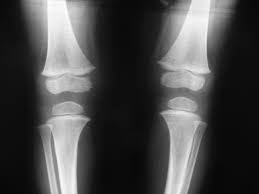

무릎 통증

무릎통증은 왜 발생할까요?

무릎 뒤쪽에 발생하는 통증은 다양한 원인에 기인할 수 있습니다.

아래는 무릎 뒤쪽 통증의 일반적인 원인 중 일부를 나열한 것입니다:

(3) 무릎 뒤쪽의 염증성 관절 질환

류마티스 관절염이나 골다공증과 같은 염증성 관절 질환은 무릎 뒤쪽에 통증을 일으킬 수 있습니다.

무릎 통증 원인

무릎 통증 원인은 어떤게 있을까요